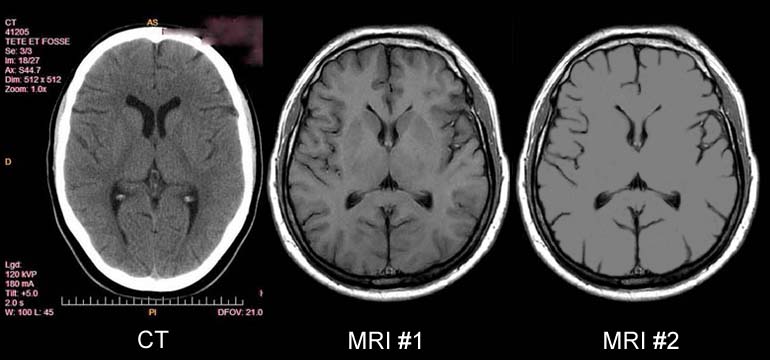

Figure 11.

T2 MRI visualization of a tumor of the brain made possible

by the discovery

of Damadian of the abnormal T2 (and T1) MR (NMR) relaxations

of cancerous tissue.

Figure 14 is an axial (cross-sectional) image of the brain showing a tumor of the cerebellum (white areas) in the midline. Figure 14c is a magnified image showing the picture elements or "pixels" (small squares) that make up the image. The cerebellar tumor as it would appear (D) with no MR signal differences. Figure D is the same image as B but where all MR signal differences were eliminated and all the MR pixels therefore had the same pixel brightness. The absence of the MR signal differences between cancer and normal tissue discovered by Damadian gives the MR image pixels equal brightness and the tumor becomes Invisible. |

Were the amplitudes of the NMR signals (fig.9) used to set the brightness of each MRI image pixel the same for all tissues (and prior to Dr. Damadian's discovery such NMR tissue signal differences were not known to exist) the brightness of each image pixel would be the same. The MR image would be a blank.

The NMR signal differences discovered by Damadian (Figs 6,9,tables 1 & 2) vary the brightness of the pixels that make up the image (Figs. 6,9). The signal differences of diseased and normal tissues generate the large differences in pixel brightness that enable all diseased tissues (cancerous as well as non-cancerous) to be exquisitely visualized (fig.3b,10,11-13) by the MRI image. Additionally the exceptional NMR signal differences among the normal tissues discovered by Damadian give rise to the extraordinary detail of normal anatomy visualized by MRI (figs. 7,8)